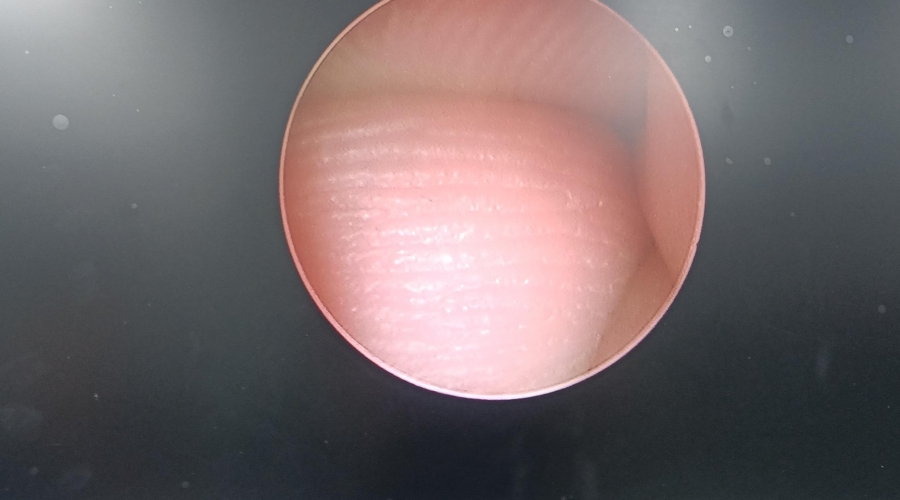

| 故障內(nèi)容 | 圖像模糊,棒透鏡破碎。 |

| 維修方案 | 更換棒透鏡 ,校對(duì)圖像,內(nèi)窺鏡抗震蕩抗沖擊性能測(cè)試,內(nèi)窺鏡密封性性能檢測(cè);內(nèi)窺鏡抗震蕩性能測(cè)試,內(nèi)窺鏡冷熱沖擊性能檢測(cè)。 |